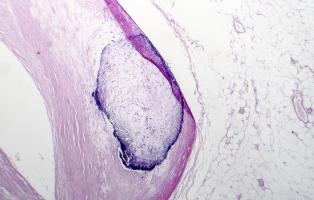

ATHÉROSCLÉROSE : Des nanoplastiques à côté de la plaque

ATHÉROSCLÉROSE : Mais comment stabiliser la plaque ?

Actualité publiée le 19/07/2022ATHÉROSCLÉROSE : Le laser qui vaporise la plaque

ATHÉROSCLÉROSE : La lipoprotéine A, le « meilleur » marqueur de risque ?

Actualité publiée le 08/04/2022ATHÉROSCLÉROSE : 40% des adultes en bonne santé ont des dépôts dans les artères